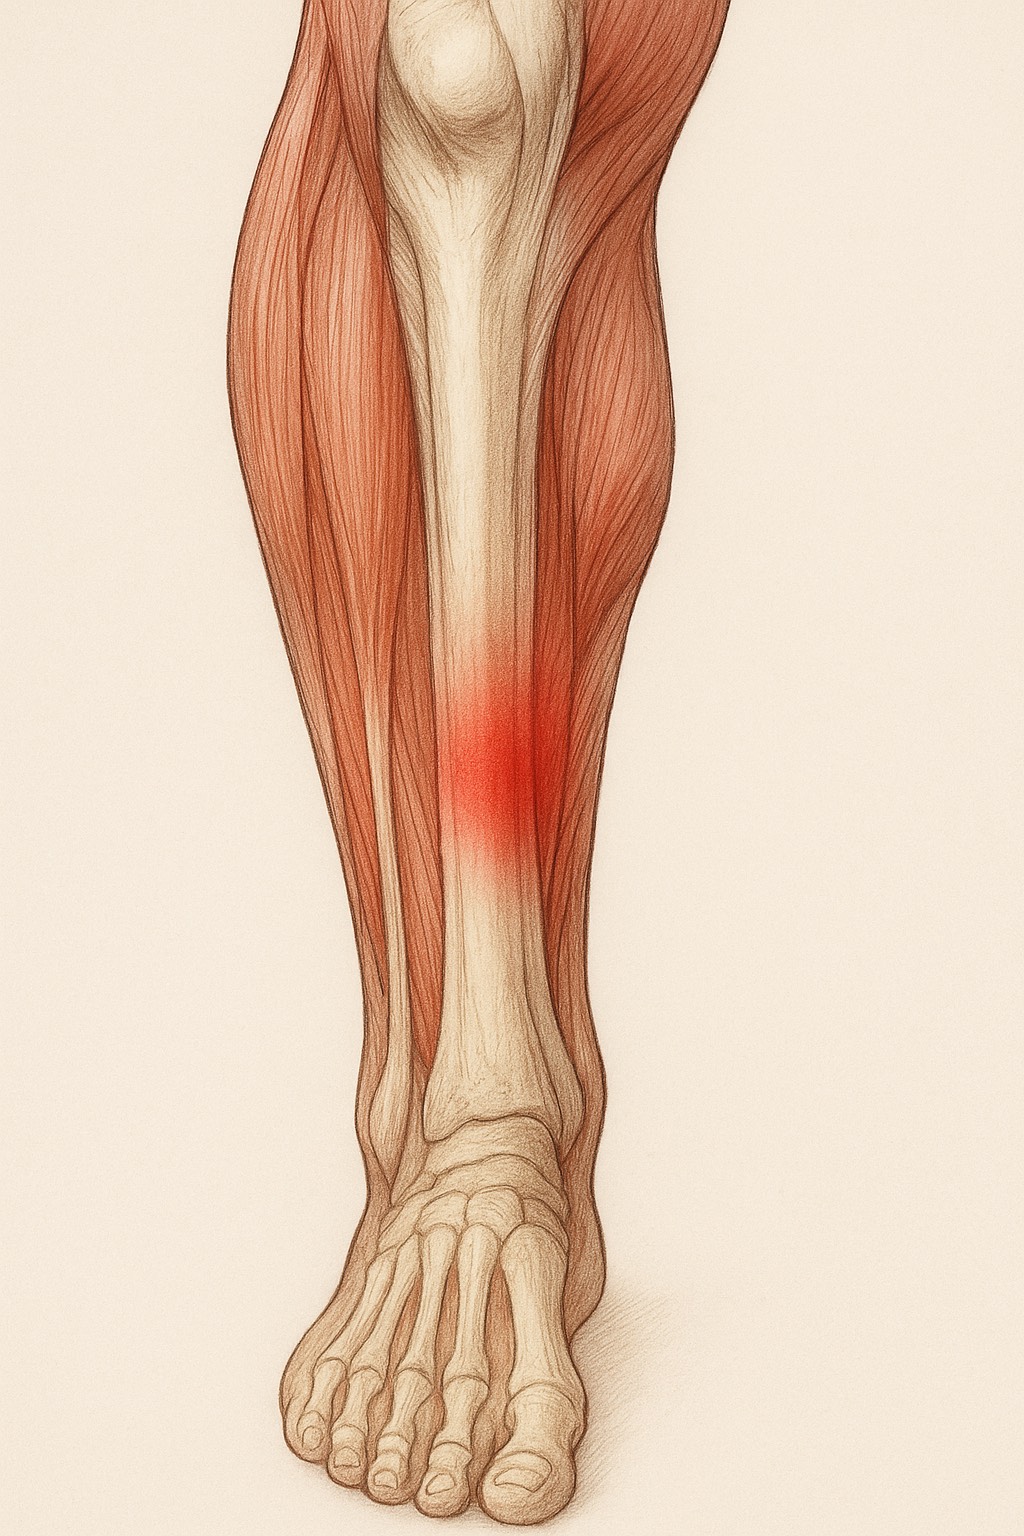

膝のお皿(膝蓋骨)のすぐ下、スネの骨(脛骨)にある

出っ張り部分が強く引っ張られることで炎症が起こり、

膝の下が腫れて痛みを感じます。特に走る・跳ぶ動作を

特に太ももの前の筋肉(大腿四頭筋)が硬くなると、膝の下にある脛骨粗面が強く引っ張られ、炎症や痛みの原因になります。

- 硬くなった大腿四頭筋やふくらはぎを緩めて、膝への負担を減らす

- 血流を改善し、回復を促す